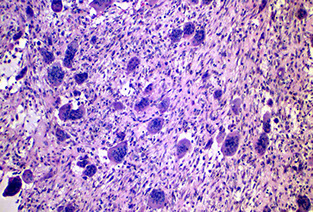

Pigmented large epithelioid cells c smaller primitive cells

Smaller primitive cells in nests

Pigmented (Melanocytic) Neuroectodermal Tumor of Infancy

Rare tumor of oral cavity and gums usually seen around birth, of neural crest origin (bc expresses melanotransferrin [involved in iron metabolism])

- grows rapidly, around midline or maxillary area

Micro: biphasic c melanin-containing cells and neuroblast-like cells

IHC: (+) S100, CK, HMB45, Melan A, NSE, CD57

Tx: excision

Px: B9, but can be locally aggressive and undergo malig changes